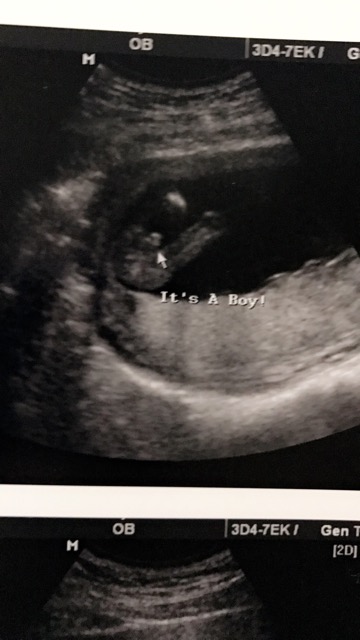

Its A Boy 💙💙💙🙈

Sooo excited for my baby boy 💙 15weeks 2days.. Went to a private clinic couldng wait 5 more weeks . Excited 👍🏻